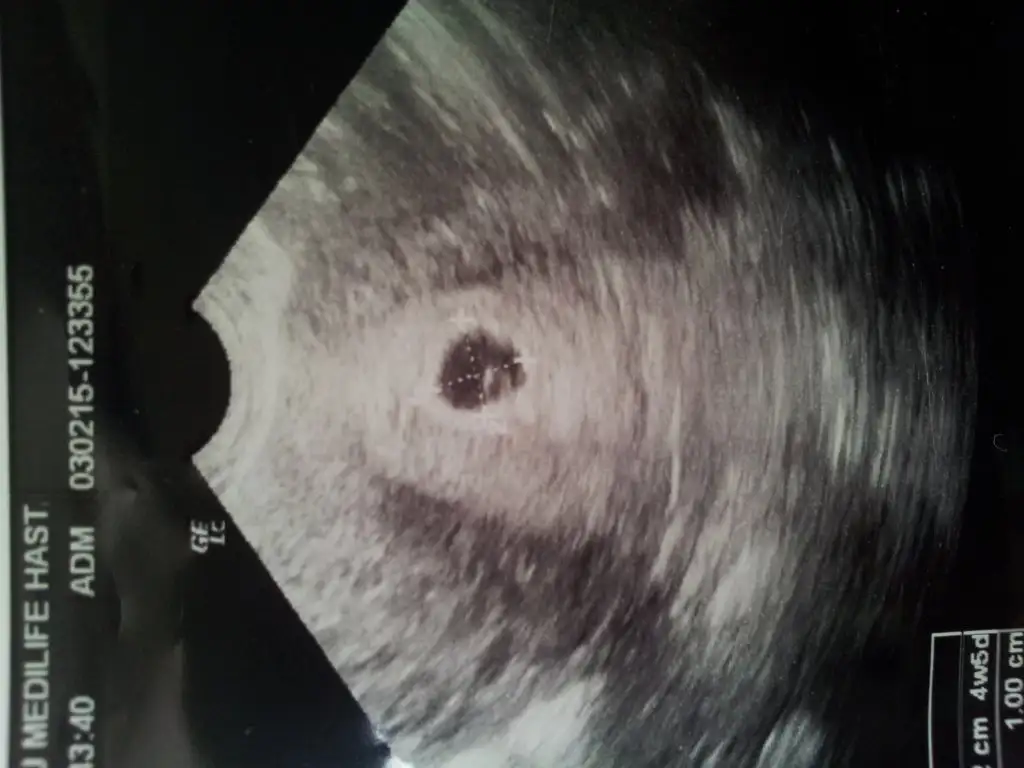

canım ben bu konuyu dr a sormustum ymun gelişip çatladığı taraf daha çok ağrırmış.. benim hamile kaldığım ay sağ tarafımda çok ağrım vardı hatta dış gebelikten şüphelenmişlerdi sonra 6. haftada doktorum sağsan yumurtlamışsın ağrı bu yüzden dedi . ama bebek cinsiyetiyle ne kadar ilgisi var bilmiyorum kızıma soldan yumurtlamıştım sol tarafımda hissettim hep bu konuyla ilgili bir topik vardıBenim soruları gören yok ama ben yine sorayım

Benim hep sağ kasığım ağrırdı bu ay sol kasığım ağrıyor.yum takibi yaptıranlar yumun geliştiği taraf mı ağrıyor acaba? Bir de sağ sol olayına ne diyor hamile arkadaşlar.bu ay denemeye karar verdim inşallah.